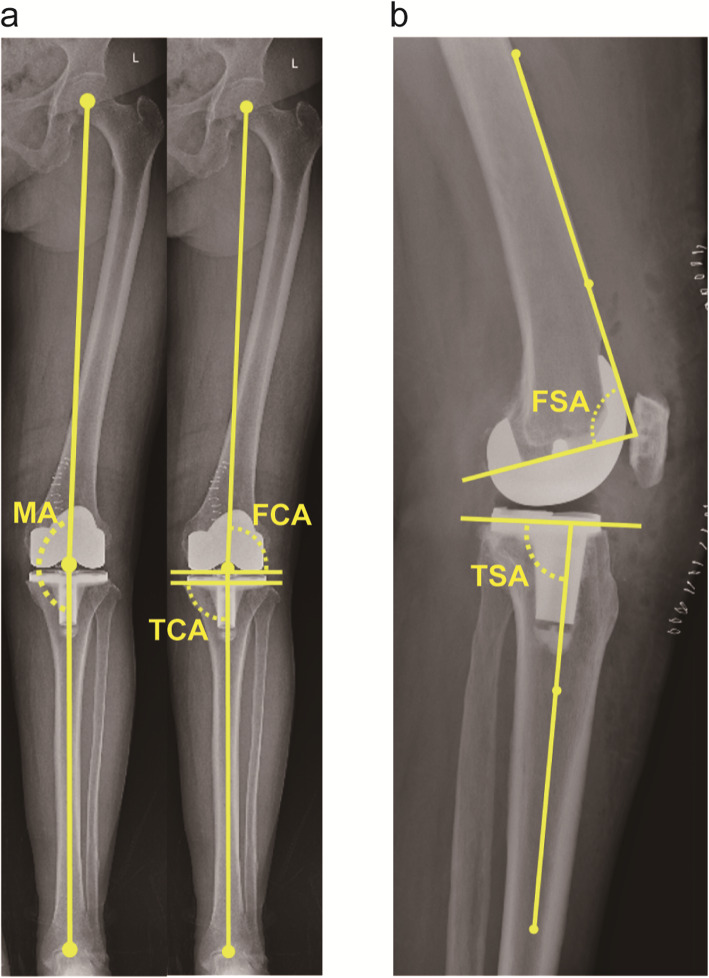

Three radiographic measurements were carried out on the AP hip-to-ankle radiographs (Fig. 1a): (1) lower extremity MA, which was formed by the angle bisecting the center of the femoral head, the center of the knee joint, and the center of the talus [12]; (2) femoral coronal angle (FCA), the lateral angle between femoral MA and intercondylar line; (3) tibial coronal angle (TCA), the medial angle between the tibial MA and the line parallel to the tibial tray. Two measurements were performed on the lateral films (Fig. 1b): (1) femoral sagittal angle (FSA), the posterior angle between the anterior cortical axis (the line linking two points of the anterior cortex at 5 and 15 cm proximal to the joint line [18]) of femur and the slope of distal femoral cut; (2) tibial sagittal angle (TSA), the posterior angle between the proximal anatomical axis (the line linking midpoints of outer cortical diameter at 5 and 15 cm distal to the knee joint [19]) of tibia and the slope of the proximal tibial cut. Absolute deviations of aforementioned angles were calculated as the absolute value of difference between the exact and ideal value (MA, 0°; FCA, 90°; TCA, 90°; FSA, 87°; TSA, 83° [20]). In line with the consensus of most research, absolute deviations of these angles were defined as norms if within 3°, otherwise they were regarded as outliers [21–23].

Fig. 1.

a Long-leg standing AP film for radiographic measurements in the coronal plane, including MA, FCA, and TCA. b Lateral radiograph for measuring component alignments in the sagittal plane, including FSA and TSA. Abbreviations, MA, mechanical axis; FCA, femoral coronal angle; TCA, tibial coronal angle; FSA, femoral sagittal angle; TSA, tibial sagittal angle